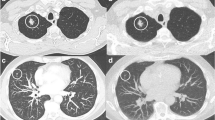

Representative cases of standard dose and ultralow dose CT are given in Figs. 5 and 6.

Representative transverse CT sections of the lung in a 33-year-old woman with a body mass index of 23.6 kg/m2 scanned with standard dose (A) at 110 kVp and 38 mAs (effective dose, 1.1 mSv; size-specific dose estimate, 3.09 mGy) and ultralow dose (B) at 100 kVp and 70 mAs (effective dose, 0.14 mSv; size-specific dose estimate, 0.37 mGy). The solid pulmonary nodule in the right lower lobe was detected in ultralow dose CT by both readers (i.e., true positive finding). Representative transverse CT sections of the lung in a 79-year-old man with a body mass index of 24.9 kg/m2 scanned with standard dose (C) at 100 kVp and 62 mAs (effective dose, 1.33 mSv; size-specific dose estimate, 3.1 mGy) and ultralow dose (D) at 100 kVp and 70 mAs (effective dose, 0.13 mSv; size-specific dose estimate, 0.3 mGy). The subsolid pulmonary nodule in the right upper lobe was detected in ultralow dose CT by both readers (i.e. true positive finding)